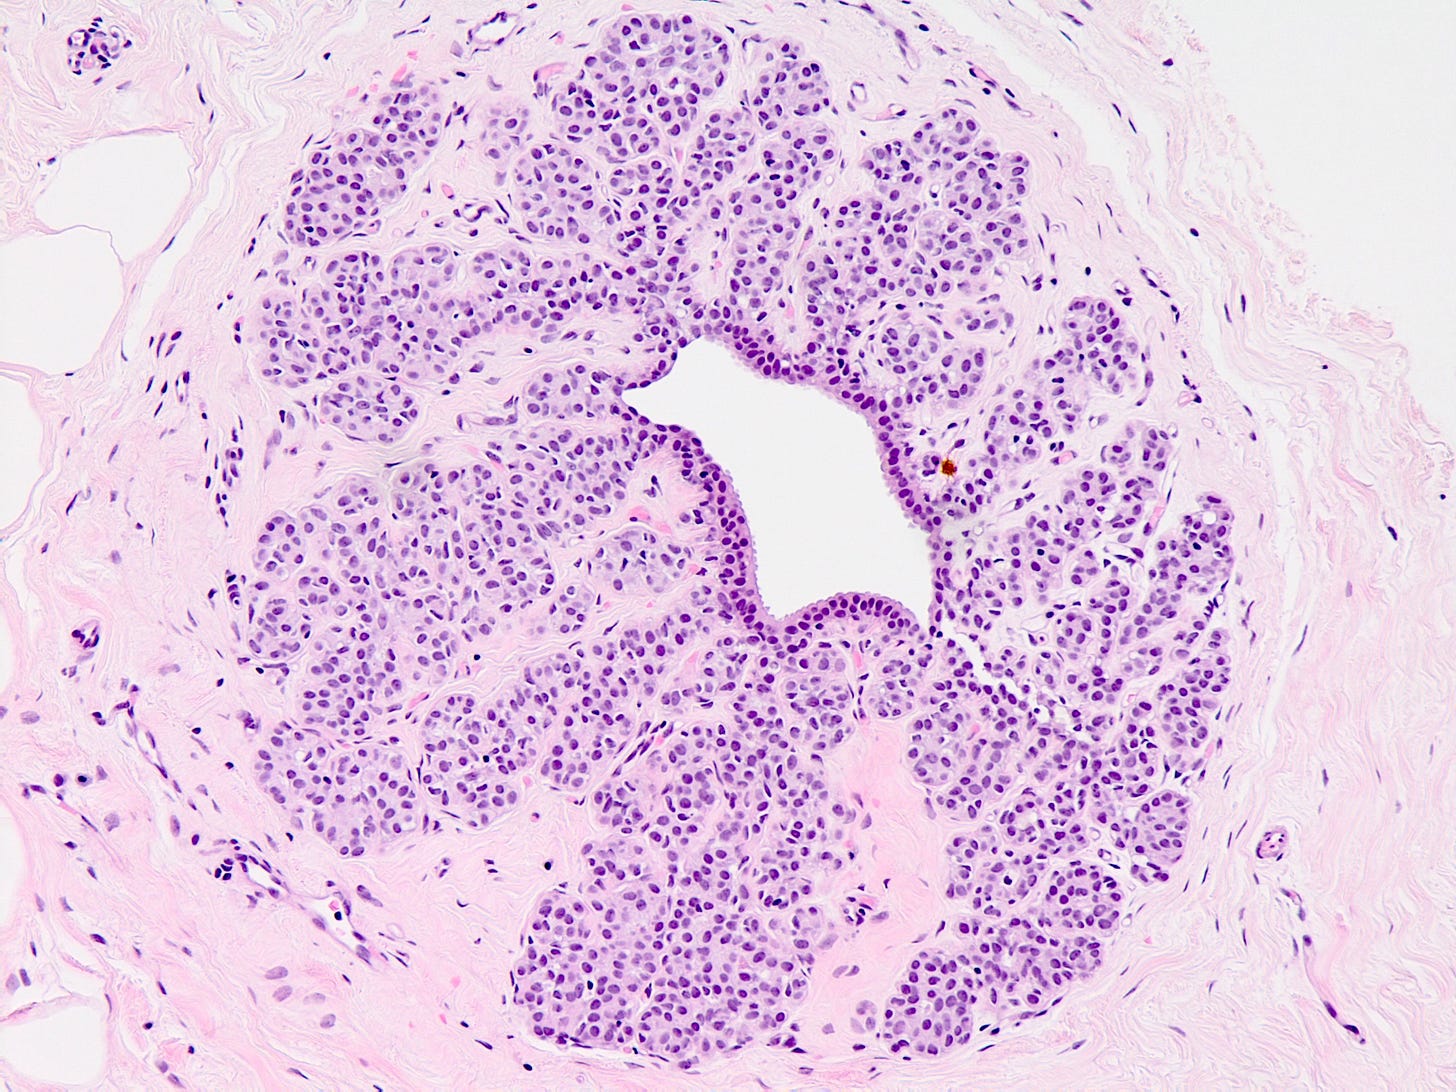

Ductal carcinoma in situ (DCIS) is a neoplastic proliferation of breast ductal epithelial cells within the ductal-lobular system with malignant microscopic features but without evidence of invasion through the epithelial basement membrane or myoepithelial cell layer into the surrounding stroma.

DCIS includes a heterogeneous group of lesions in terms of microscopic appearance, molecular alterations, biomarker expression profile and biologic potential for progression to invasive carcinoma. It is divided into low grade (less aggressive) DCIS and high grade DCIS. Normal breast tissue appears to transform to only one of these entities through two distinct molecular pathways (i.e. high grade DCIS does not typically arise from low grade DCIS). Low grade DCIS shows frequent chromosomal losses at 16q. High grade DCIS shows frequent losses at 8p and gains at 17q and has a similar molecular profile as invasive breast cancer.

DCIS - microscopic images